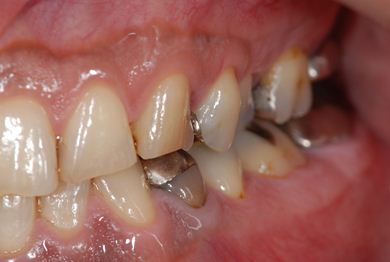

インプラントの症例写真 IMPLANT

インプラント治療+セラミック治療+歯肉歯槽骨整形術

| 性別/年齢 | 男性 / 47歳 | ||||||||||||||||||||||||||||||||

| 主訴 | 悪いところの治療と、歯をきれいにしたい。 | ||||||||||||||||||||||||||||||||

| 治療方針 | 右下奥、保存不能な歯を抜歯し、インプラント治療にて、機能的・審美的回復を行う。 | ||||||||||||||||||||||||||||||||

| 治療内容 | インプラント2本、メタルボンドセラミッククラウン9本(メタルボンド用土台6本)、ハイブリッドセラミッククラウン2本(セラミック用土台2本)、ハイブリッドセラミックインレー5本、歯肉歯槽骨整形術 | ||||||||||||||||||||||||||||||||